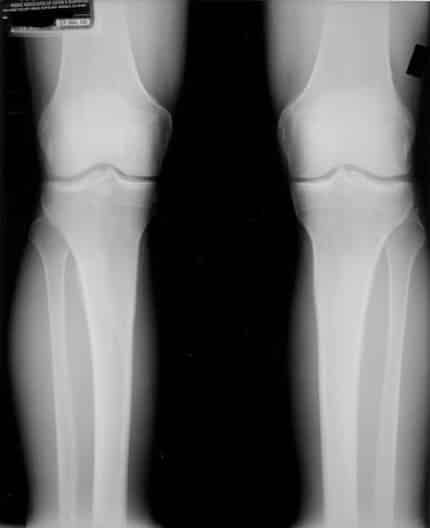

Deze röntgenfoto is van een cliënt van een Egoscue-kliniek (de methode waarop houdingstherapie is gebaseerd) in Austin, Texas. Deze is aan de slag gegaan met uitsluitend houdingstherapie-oefeningen. Iets meer dan een jaar later heeft hij weer röntgenfoto’s laten maken. Zie de foto hieronder.

Zoals u kunt zien, is het kraakbeen teruggegroeid. De knie lijkt weer als nieuw. En de klachten waren verdwenen. Dus het kan zeker, kraakbeen laten teruggroeien. Het lichaam moet alleen de kans krijgen om het kraakbeen te laten groeien zonder dat het steeds weer wordt afgesleten. Op het moment dat het gewricht in de juiste, neutrale, stand is, zal het kraakbeen niet langer wegslijten. Het is een beetje als dweilen met de kraan open: zolang de kraan open staat, kun je bezig blijven. Doe eerst maar de kraan dicht, pak eerst de echte oorzaak aan.